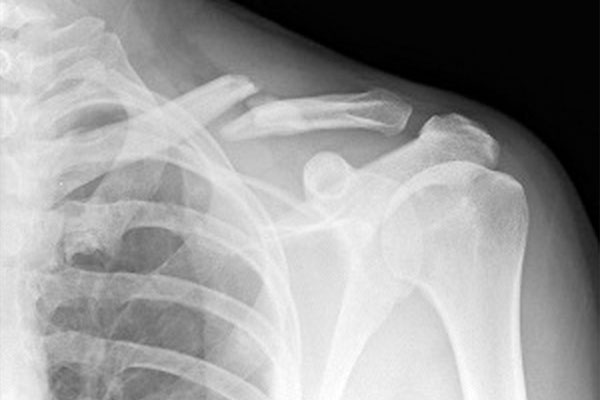

شکستگی پا به وجود شکستگی یا ترک در یکی از استخوانهای پا گفته میشود. شایعترین دلایل آن عبارتند از زمین خوردن (سقوط)، تصادفات با وسایل نقلیه موتوری و آسیبهای ورزشی.

نحوه درمان شکستگی استخوان ران و ساق پا به محل و شدت آسیب بستگی دارد. ممکن است برای پاهایی که دچار شکستگی شدید شدهاند نیاز باشد که از طریق عمل جراحی ابزارهایی در درون استخوان شکسته قرار داده شود تا استخوان، در دوره بهبود، راستای خود را حفظ کند. شکستگیهای کم شدتتر را نیز میتوان با گچ یا اسپلینت (آتل) درمان کرد. در همه موارد، تشخیص و درمان سریع شکستگی استخوان ران و ساق پانقش مهم در بهبودی کامل آن دارد.